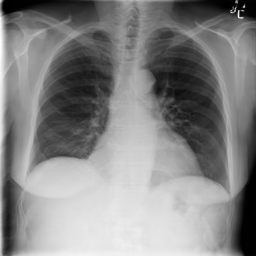

Experiment Setup

We used the NIH Chest X-ray 14 [73] dataset to conduct our experiments. This dataset consists of labeled chest X-ray images, from over unique patients corresponding to 14 common thoracic disease types, including atelectasis, cardiomegaly, effusion, infiltration, mass, nodule, pneumonia, pneumothorax, consolidation, edema, emphysema, fibrosis, pleural thickening, and hernia. The dataset is divided into training, validation, and testing sets, containing , . and images, respectively444We followed the dataset splits in https://github.com/zoogzog/chexnet/tree/master/dataset. Our experiments were designed to examine and compare four training methods:

Figure 7 samples real and GAN-generated images. The first column presents real images, the second column GAN-generated unsupervised, and the third GAN-generated supervised. The GAN-generated images may successfully fool our colleagues with no medical knowledge. However, as reported in [63], the GAN-generated labeled chest X-ray images must be screened by a team of radiologists to remove erroneous data (with respect to diagnosis knowledge). Without domain knowledge, incorrectly labeled images may be introduced by GANs into the training pool, which would degrade classification accuracy.

| Real | GAN unsupervised | GAN supervised |